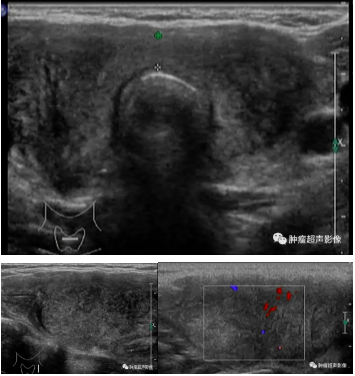

颈部疼痛,双侧甲状腺肿大,形态不规则的低回声,边界模糊不清,回声不均匀,病灶回声从外向内降低,甲状腺前方包膜模糊不清,与颈前肌间的间隙消失,CDFI血流稀少。